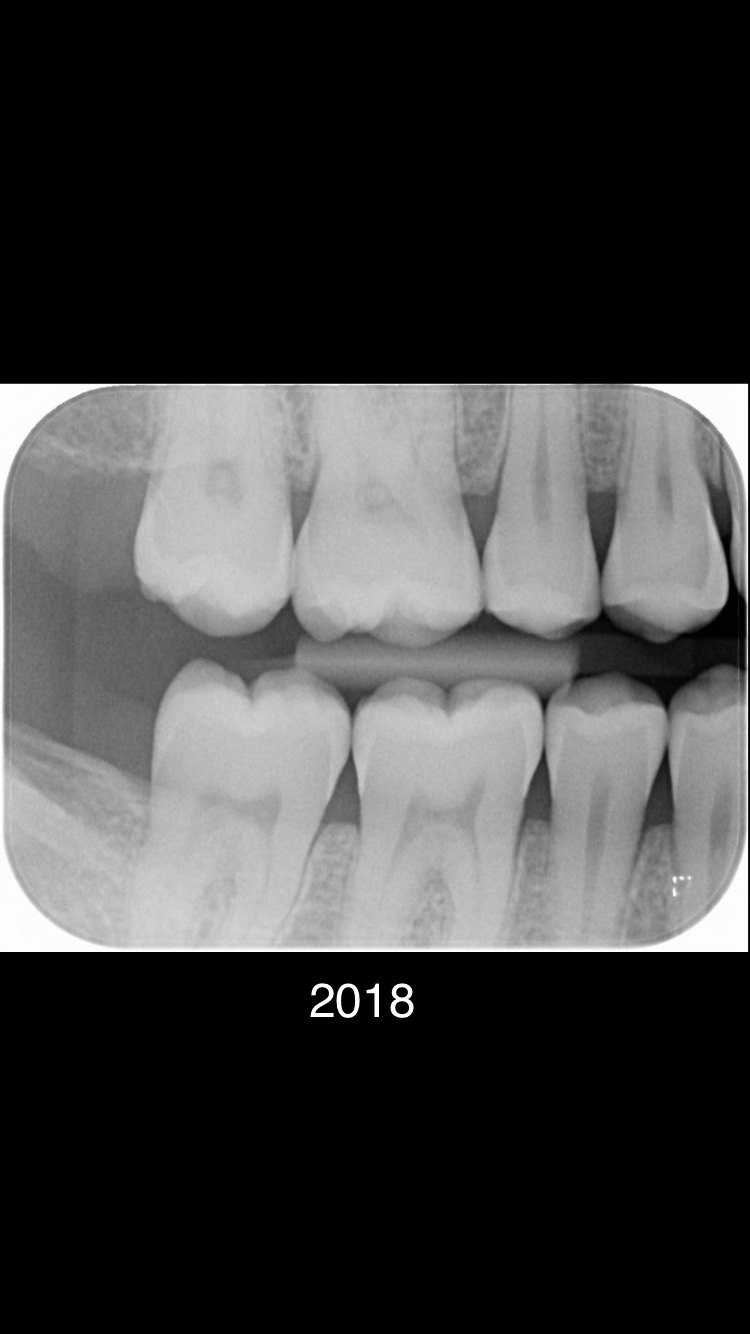

Ik ben heel erg benieuwd of er sprake is van gaatjes in dit gebit. Tot en met 2021 waren er geen gaatjes geconstateerd. Ivm gestopte tandarts (was werkzaam als zelfstandige tandarts praktijk) en praktijk overname spreekt de nieuwe tandarts (werkzaam in een tandartsenpraktijk met meerdere tandartsen) van ruim 7 gaatjes. Kunt u aangeven of dit klopt?

Er zijn meerdere beginnende plekjes maar die zijn nog niet door het glazuur dus hoeven nog niet aangepakt te worden. De vier in de linker boven en onderkaak gevonden "gaatjes" zou ik ook aanpakken. 25.26.35,36.......24 kan ik niet goed beoordelen dus twijfel.16 zou ik nog niet doen. In 2021 waren er links enige die net wel of net niet door het glazuur zijn.. dus ik kan begrijpen dat uw tandarts dat in de gaten heeft gehouden, gemonitord. Maar wat heeft u gedaan tussen 2020/2021 en 2023.. Gebruikt u wel ragers elke dag???>of andere reiniging hulpmiddelen voor tussen de tanden en kiezen. Let op uw voeding/drank gebruik... beperk het aantal invloed momenten op uw gebit tot 6. etc etc. dit gaat fout. Op de status praesens v uw gebit zie ik maar 5 aantekeningen niet 7. Maar ik ben niet goed in rekenen.

Bedankt voor uw reactie. Ik heb in de afgelopen dagen 2 tandartsenpraktijken bezocht, de eerste gaf aan dat er 5 gaatjes zijn. De tweede tandarts vertelde dat er 3 gaatjes zijn, ze noemde 25, 26 en 36. Verder noemde ze vier opkomende gaatjes. Maar ik weet niet waar precies.

Tandarts, als ik het goed begrijp bedoeld u dat u ook ziet dat ik gaatjes heb? Ik heb tot vorige week begrepen dat m’n voormalige tandarts zei dat ik geen gaatjes zou hebben. Links onder heb ik de afgelopen 2 jaar op en af wel een kloppend gevoel gehad, maar m’n tandarts gaf aan dat ik een mondbitje moest dragen bij slapen.

Begrijp ik dat uw advies is dat ik vier tanden de linker boven en onderkaak 25.26.35,36 nu het beste kan laten vullen?

Ik vroeg me ook af of u verstandig vind dat ik nummer 35 en 16 moet laten vullen?

Ik heb uw vorige bericht gelezen. Alleen vroeg ik mij af wat u bedoeld met quote: De vier in de linker boven en onderkaak gevonden "gaatjes" zou ik ook aanpakken. 25.26.35,36.......24 kan ik niet goed beoordelen dus twijfel.16 zou ik nog niet doen unquote.

Ik zie “gaatjes” tussen haakjes staan, vandaar dat ik in de war ben. Bedoeld u dat u 25 , 26, 35 en 36 ook ziet als gaatjes die ik het beste kan laten vullen?